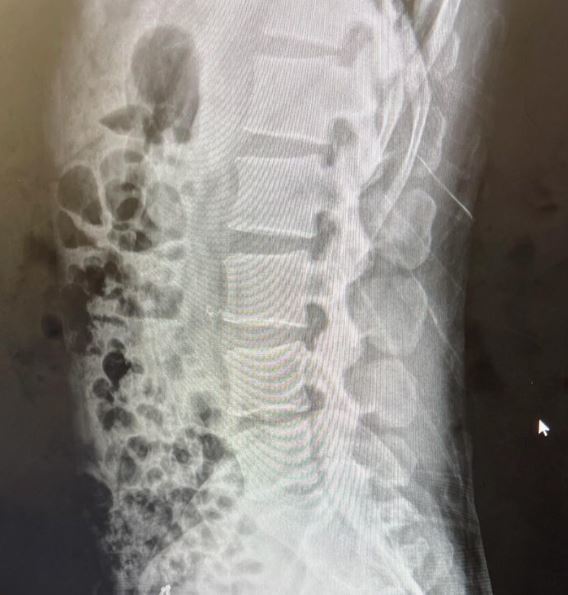

최근 홍석천은 인스타그램에 허리 엑스레이 사진을 공개했다. 그는 허리디스크로 고통을 느끼고 있다.

홍석천은 "디스크가 안 좋단다"라며 "오랫동안 참 애썼다. 고통은 둘째고 왠지 서글프다"라고 말했다.

img_20241103115248_2144bbfa.jpg 허리 디스크 인증 사진 / 홍석천 인스타그램